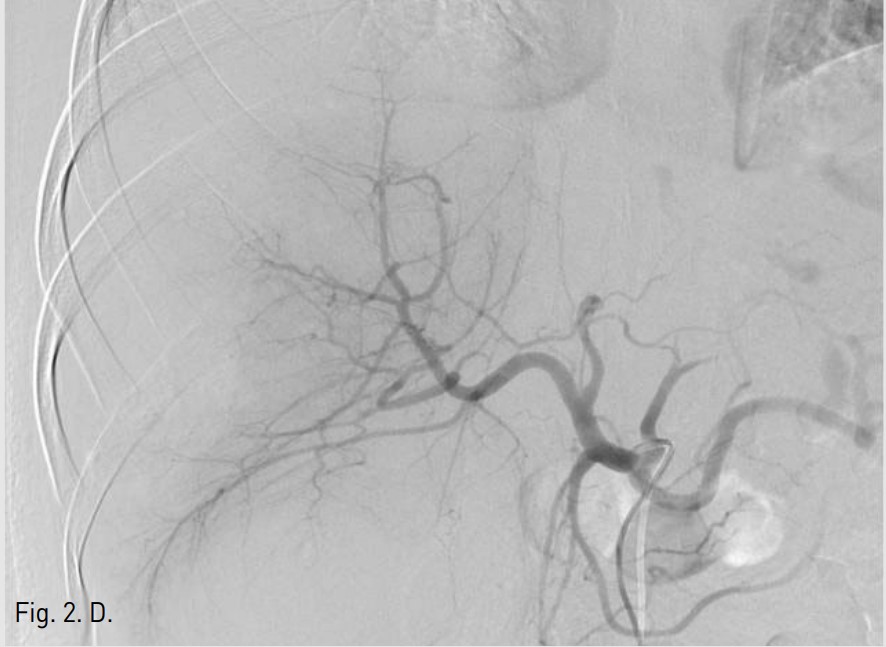

5F RH catheter (Cook, Bloomington, USA)를 이용하여 바로 시행한 간동맥조영술에서 right posterior inferior hepatic branch에서 급성출혈이 관찰되었다(Fig. 1B). 2.9F coaxial microcatheter(Stride, ASAHI, Aichi, Japan) 로 출혈혈관부위를 초선택한 후 gelatin sponge(Cutanplast, Mascia Brunelli , Milan, Italy)을 이용하여 색전술을 시행하였다(Fig. 1C). 시술 다음날 혈색소 수치는 10.0g/dL로 증가하였다. 그러나 시술 2일 후 환자의 활력징후는 혈압 131/80mmHg, 맥박수 82/min로 안정적이었지만, 혈색소가 7.8g/dL로 급격히 감소하였고, 우상복부에 심한 통증을 호소하여 재출혈의 의심하에 복부 CT검사를 시행하였다. CT검사에서 간에 다량의 피막하 혈종이 관찰되었지만, 조영제의 혈관외 유출은 보이지 않았다(AAST grade Ⅲ)(Fig. 2A). 같은 날 시행한 간동맥 혈관조영술에서 기존 색전술을 시행한 동맥에서의 재관류는 없었지만, 새로 생긴 다른 부위의 피막하혈종 내로 광범위한 다발성 미세출혈이 관찰되었다(Fig. 2B). Microcatheter를 이용하여 각 출혈부위 근처의 segmental artery들을 선택한 후 gelatin sponge를 이용하여 광범위한 부위에 색전술을 시행하였고, 더 이상의 출혈은 관찰되지 않았다(Fig. 2C, D). 시술 후 환자의 혈색소는 정상화되었고 우상복부 통증은 점차 감소하였다. 이 후 뚜렷한 합병증 없이 입원 1달 후 퇴원하였다.

Fig. 2. B

Fig. 2B. Celiac angiogram during second embolization shows multiple tiny contrast extravasations in right subcapsular area (arrows).